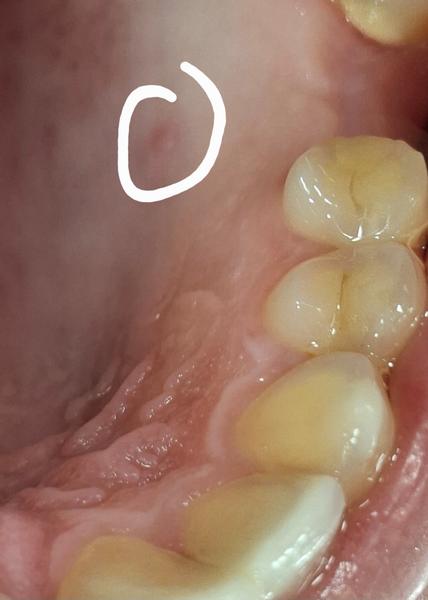

Malá hrčka na podnebí

prosim o radu, v ustach na hornom podnebi sa mi spravila mini hrcka, kazde dva mesiace sa mi mierne zvacsi ako keby zduri a nasledne za 2 -3 dni zasa vstrebe na mini rozmer, neboli len si ju citim jazykom. Trva to uz rok, zubarka mi to nevedela presne identifikovat ale mysli si ze by to mohla byt mini cysta na slinnej zliazke. Prikladam aj foto v stave zdurenom, v kludnom stave ju skoro nevidiet. Mate s niecim takymto skusenost? Pojdem zubnemu chirurgovi tak sa mi na to pozrie, len ma zaujima ci s tym niekto ma skusenost a ako sa to riesi? dakujem.